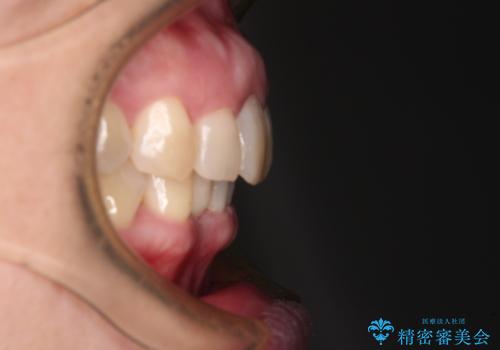

- 下顎前歯が抜けそうとのことで来院された患者様です。

初診の状態ではすぐにでも抜けそうな状態で、インプラントによる補綴治療を行うこととしました。

インプラント治療に際し、前歯の叢生に対する矯正治療を提案したところ、興味を持たれたので、インビザライン・ライトによる矯正治療を行うこととしました。

抜歯後にスペースができると恥ずかしいため、抜歯した歯を接着剤で固定した上で矯正治療を行い、その後インプラントやオールセラミッククラウンの装着を行うこととしました。